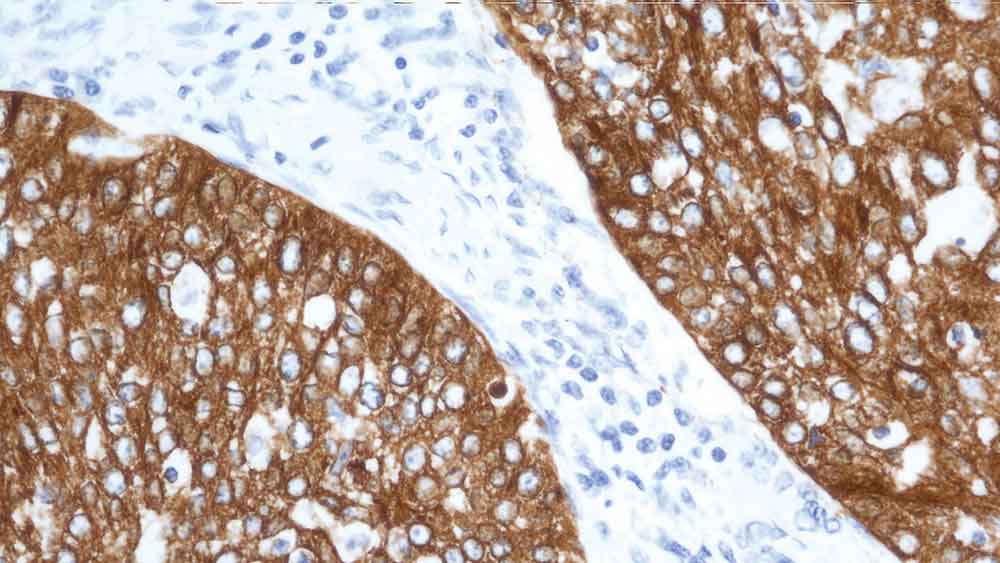

Human rectal adenocarcinoma: immunohistochemical staining for Cytokeratin 19. Note: cytoplasmic staining of malignant epithelial cells. Cytokeratin 19: clone b170

Das kleinste humane Cytokeratin-Intermediärfilamentprotein (40 kD) wurde als Cytokeratin 19 identifiziert; es wird in einer Vielzahl an Epithelzellarten, darunter auch zahlreichen Duktus- und Drüsenepithelgeweben exprimiert.

NCL-CK19 führt zu einem komplexen heterogenen Färbemuster beim nicht-keratinisierenden Plattenepithel und in Haarfollikeln, wobei eine starke Anfärbung der Basalschicht beobachtet wird.